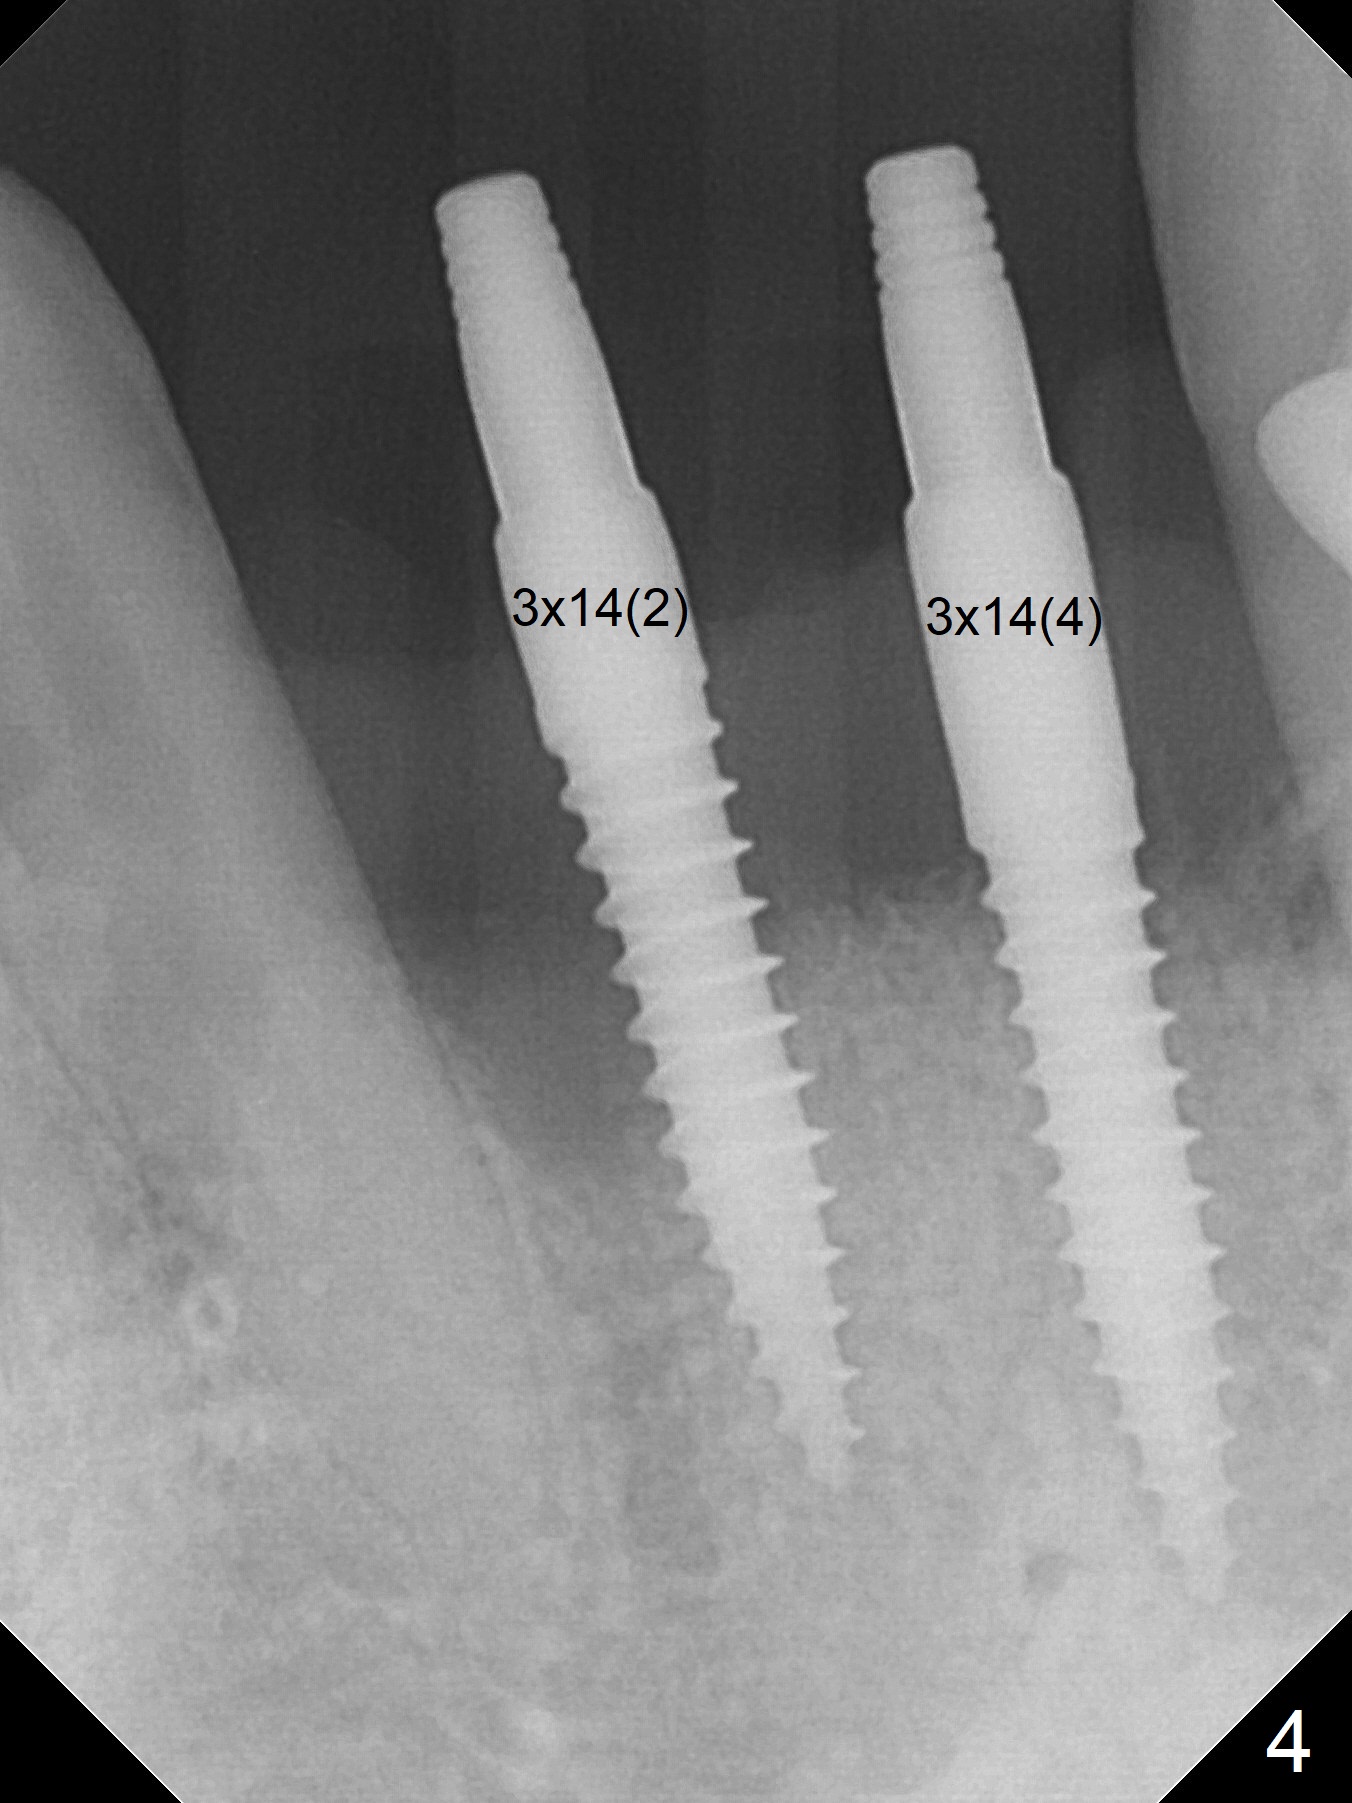

After extraction of 4 of the lower incisors, there are basically 2 sockets (#23/24 and 25/26), separated by the apparently midline bone (Fig.1 red line).  In spite of using Lindamann bur to move the 25/26 osteotomy mesially, a 3x14(2) mm dummy implant remains close to the tooth #27 (Fig.2).  The terminal branch of the Incisive Canal (<) is located between the lateral and central incisors.  A de novo osteotomy (Fig.3 (1.5 mm drill)) is made mesial to the original one (O).  While the 3x14(2) mm dummy implant is incompletely placed at #25/26, a 3x14(4) mm 1-piece one is placed at #23/24 (Fig.4).  Finally the same implant is placed at #25/26 with placement of mineralized cortical/cancellous bone (Fig.5 *).  When the large sockets are sutured, the supraerupted teeth #7-9 touch the lower gingiva (Fig.6).  The incisal edge is reduced for clearance (Fig.7).  Periodontal dressing is less likely to be dislodged with the incisal edge reduction (Fig.8,9).  A provisional FPD is fabricated 1 week postop.  Hard (Fig.10) and soft (Fig.11,12) tissues heal 5.5 months postop.  The patient returns for crown cementation 3 months post impression (9 months postop, Fig.13,14).